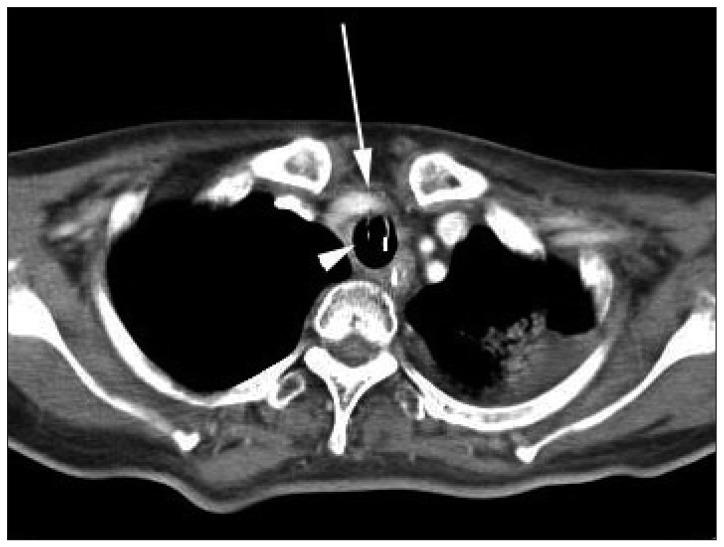

Tracheoinnominate artery fistula is a critical complication of tracheostomy. The most important factors influencing patient outcome are prompt diagnosis, immediate control of bleeding with a patent airway, and emergency operation with or without interruption of the innominate artery. Here, we report a case of tracheoinnominate artery fistula in a 40-year-old woman with cerebrovascular accident who was successfully managed with an aorta-axillary artery bypass.

气管无名动脉瘘是气管切开术的一种严重并发症。影响患者预后的最重要因素是及时诊断、在气道通畅的情况下立即控制出血以及对无名动脉进行或不进行阻断的急诊手术。在此,我们报告一例40岁脑血管意外女性患者发生气管无名动脉瘘的病例,该患者通过主动脉-腋动脉旁路移植术成功得到治疗。